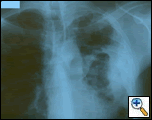

| Figure 1: PA chest film reveals a left pleural-based mass with pleural thickening and upper lobe scarring. |

PA and lateral chest film revealed patchy consolidation of the left lung with a large pleural-based mass, left apical pleural thickening, and right upper lobe scarring (Figure 1). Helical CT scan of the chest, abdomen, and pelvis with contrast demonstrates a large, 10.8 x 4.1 cm left pleural-based mass extending into the chest wall and left breast (Figure 2). There was periosteal thickening and irregularity of adjacent ribs. Multiple enlarged mediastinal, left hilar, and supraclavicular nodes were noted, the largest 1.5 x 2.6 cm in the AP window or station five region. There was patchy consolidation of the left and right upper lobes. An MRI of the thorax with contrast was obtained and confirmed the presence of left supraclavicular adenopathy and an enhancing mass with extension into the chest wall involving the ribs, infiltration of the pectoralis muscle, and extension into the left lung parenchyma. The main differential diagnoses at this time were neoplasm (sarcoma, advanced lung cancer, mesothelioma, lymphoma, osteosarcoma).